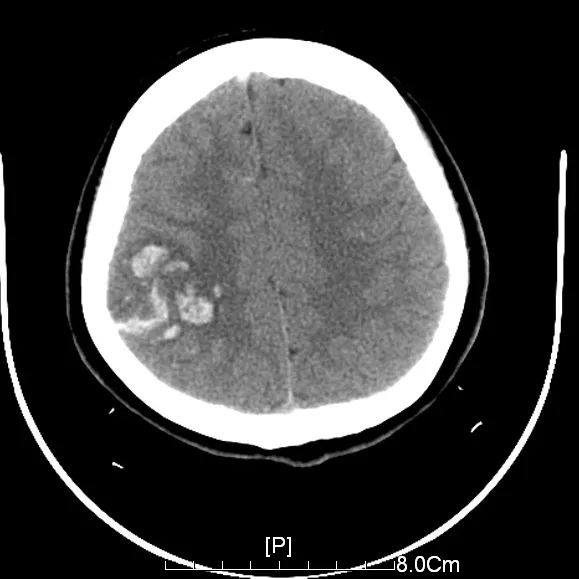

因為月經(jīng)不調(diào)、肥胖 一年多前在廈門一家醫(yī)院治療 長期服用黃體酮和達英35 16歲的漳州龍海女孩玲玲(化名) 竟引發(fā)了腦出血 差點沒命 玲玲的管床醫(yī)生、第909醫(yī)院神經(jīng)外科副主任醫(yī)師: 達英35是一種短效避孕藥,長期服用可能導致靜脈竇血栓。 玲玲是4月6日突然出現(xiàn)頭痛、頭暈和嘔吐,起初癥狀較輕,她就沒太在意。不料4天后,不僅上述癥狀加重了,而且左側(cè)完全偏癱、無法正常行走。 入院的相關檢查發(fā)現(xiàn),玲玲的頭顱皮層下有出血,醫(yī)生懷疑是靜脈竇血栓引起的腦出血。后經(jīng)靜脈竇成像檢查,明確是上矢狀竇堵塞了三分之二。 ▲玲玲的右側(cè)頂葉皮層散在出血 一般顱內(nèi)出血需要止血藥物治療,可當時玲玲的頂葉血腫使用止血藥物,不但起不到止血作用,還會加重靜脈竇血栓,導致出血增加。 一旦頂葉血腫持續(xù)增加或局部腦水腫進一步加重,則隨時都有腦疝的危險,甚至危及生命。 醫(yī)務人員不敢有絲毫大意,通過采取尿激酶溶栓、肝素鈣抗凝和改善循環(huán)等對癥措施,先后三次進行腰椎穿刺監(jiān)測顱內(nèi)壓變化情況,以及高壓氧促進神經(jīng)功能和肢體功能康復。 經(jīng)過一周的精心治療和護理,一度病危的玲玲生命體征逐漸平穩(wěn),于4月17日從重癥病房轉(zhuǎn)入普通病房進行后續(xù)治療。 目前,玲玲神志清楚、言語正常,左側(cè)肢體肌力明顯改善,顱內(nèi)壓從入院時的 400毫米水柱下降到了150毫米水腫,頭痛癥狀也基本消失。 為何避孕藥會誘發(fā)腦出血? 醫(yī)生解釋道,避孕藥含有大量孕激素,長期大量服用會使血液中的凝固成分增加,導致血液粘稠度增加與血流速度減緩,就很可能引發(fā)靜脈竇血栓。 有統(tǒng)計表明,長期大劑量服用避孕藥比未服用口服避孕藥的健康女性,深靜脈竇血栓的發(fā)生率會增加四至八倍。 醫(yī)生提醒,調(diào)理月經(jīng)服用避孕藥有不少禁忌癥,需專業(yè)醫(yī)生指導,還要定期復查各項指標,尤其是處于發(fā)育期的女性,服用避孕藥調(diào)節(jié)月經(jīng)更應格外慎重。 若在服藥期間出現(xiàn)腿痛、腿部腫脹、呼吸困難、胸痛等癥狀時,要盡快就醫(yī)檢查。